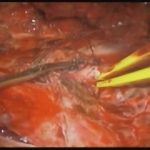

術中写真

摘出 後